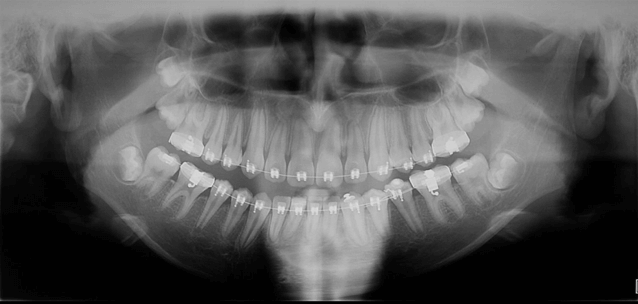

Fase de Finalización

Radiografía Panorámica Final

Radiografía Panorámica Comparativa